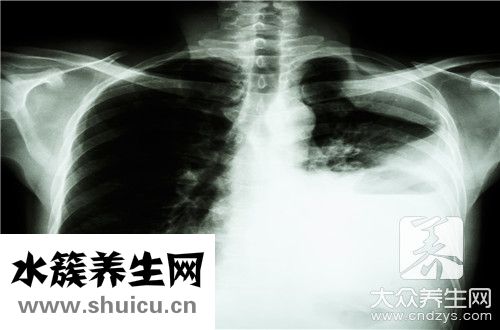

3、胸部X線檢查為確診肺結核的必需方式,可分辨肺結核的位置、范疇、變病特性、變病進度、醫治反映、判斷功效的關鍵方式 。